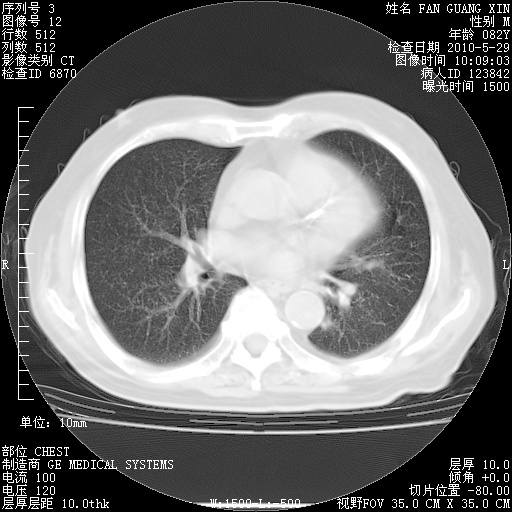

还需要哪些辅助检查?我们医院排除真菌感染没有任何检验方法,胸片好像能够排除肺部真菌感染。

补充:ENA化验全部阴性。免疫五项(IgG、IgA、IgM、C3、C4)只有C4略高。

CD3+ T细胞/淋巴细胞 46% (参考值50.00~84.00%)

CD3+CD4+ T细胞/淋巴细胞 21% (参考值27.00~51.00%)

CD3+CD8+ T细胞/淋巴细胞 25% (参考值15.00~44.00%)

CD3+CD4+ T细胞/CD3+CD8+ T细胞 0.84 (参考值0.71~2.78)

T细胞亚群是治疗5天采血。